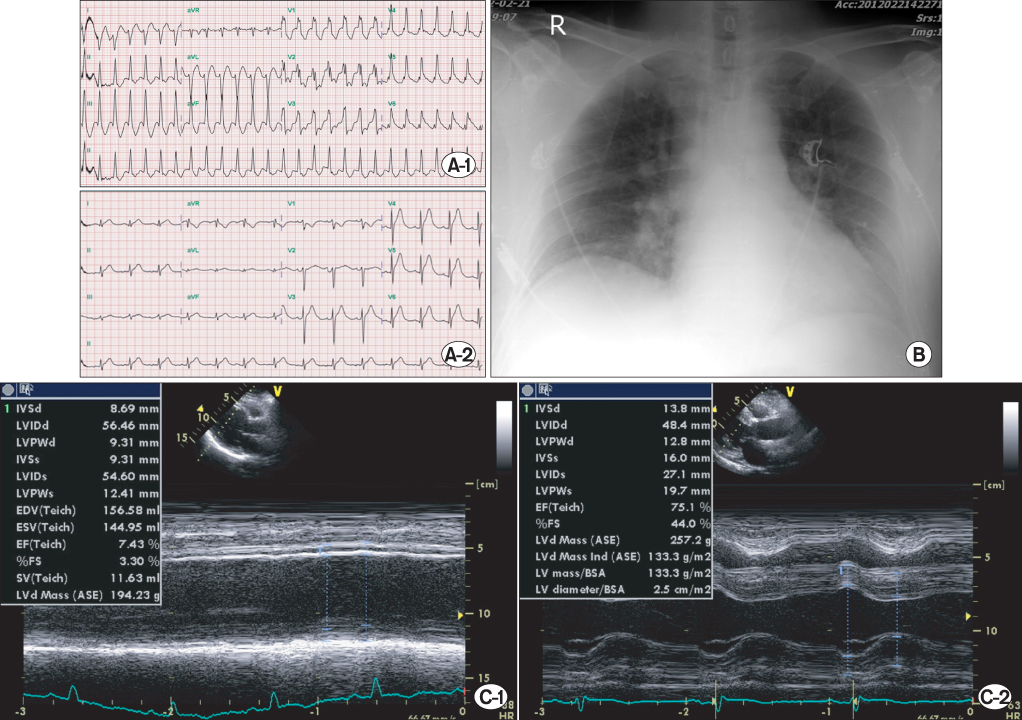

Three years after the first admission, the patient was admitted via the ER for epigastric discomfort, nausea, and headache accompanied by dyspnea and cold sweating. On physical examination, systolic and diastolic BPs were 200/100 mmHg, heart rate was 170 beats per minute, respiratory rate was 24. Chest radiography showed cardiomegaly and pulmonary edema. Initial ECG showed VT; after amiodarone loading, the rhythm returned to sinus rhythm and ST segment elevation on lead V3~6 was evident (

2 42.9 mmHg, bicarbonate 16.3, and oxygen saturation 90.3%. Levels of CK, CK-MB, and troponin-T were within normal ranges. TTE showed severe LV systolic dysfunction, EF of 10%~15%, and RWMA with severe hypokinesia and akinesia (

Fig. 2). With the support of external bypass system (EBS) and intraaortic balloon pump, an emergency CAG was performed, there were no obstructive vessels. EBS was continued for 3 days, thereafter LV contractility and wall motion was improved (EF, 50~55%) other than apical akinesia. Hospital day 12, cardiac function was fully recovered (LVEF, 72%) without RWMA.

Fig. 1Electrocardiogram (ECG), chest X-ray and transthoracic echocardiography (TTE) findings at first admission. Initially, (A) ECG shows non-specific ST change, and (B) chest X-ray shows pulmonary edema. (C-1) TTE reveals mild left ventricular (LV) systolic dysfunction, but (C-2) eight month follow-up TTE after first admission demonstrates complete recovery of LV systolic function.

Fig. 3Electrocardiogram (ECG), chest X-ray and transthoracic echocardiography (TTE) findings at second admission. Initial ECG (A-1) shows ventricular tachycardia (VT). VT is resolved (A-2) by loading of amiodarone, and ST segment elevation appears on V3?V6 leads. (B) Chest X-ray (anteroposterior image) shows pulmonary edema. (C-1) Initial echocardiography shows severe left ventricular (LV) dysfunction. (C-2) Follow-up echocardiography reveals completely normalized LV systolic function on hospital day 12.